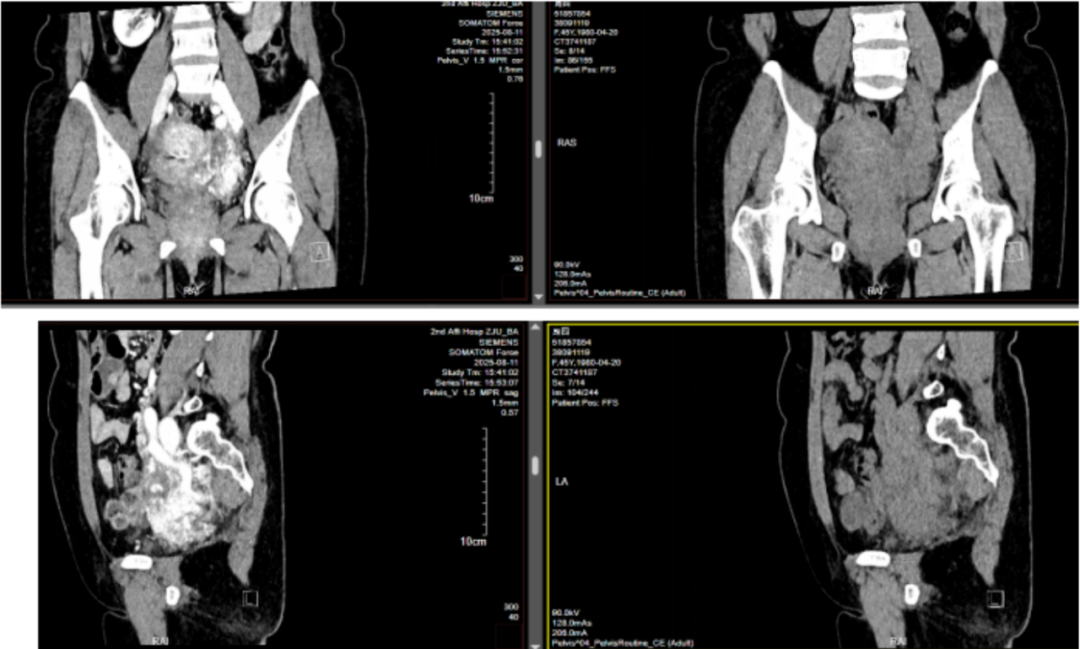

考虑到患者为女性,45 岁正是围绝经期,并且患者表示自己近 2 月有月经不规律的情况,因此又补充了妇科影像学检查。其中的盆腔增强 CT 显示,患者子宫多发肌瘤,右侧附件区囊肿,盆腔左侧血管曲张,左髂静脉、下腔静脉可疑充盈缺损。

盆腔增强 CT

「我们接诊的这位患者,盆腔血管畸形复杂程度及腹部血管内黏连程度非常大,出血风险比较高。」根据术前根据影像学结果,放射科钟建国副主任医师分析认为,想要取出患者右心房的肿瘤,一般需要建立体外循环,而体外循环所需的肝素化,可能会引起盆腔部位渗血甚至大出血。

因此,治疗团队一致决定分两步走:先由妇科团队主导,完整切除全子宫+双侧附件并处理血管畸形;再择期进行二期手术,由心脏大血管外科和普外科联合主导,打开心脏及下腔静脉「拽出」堵在血管里的剩余肿瘤部分。

术前根据影像学结果充分评估后,治疗团队认为可能较难实现从心脏一次性将血管内肿瘤全部取出,如果取不完整,还需要增加再次开口操作,或造成术后复发,既然如此,那就再次分段:分别从心脏和下腔静脉打开入口,将剩余瘤体分为上下两段分别从上下两端取出。